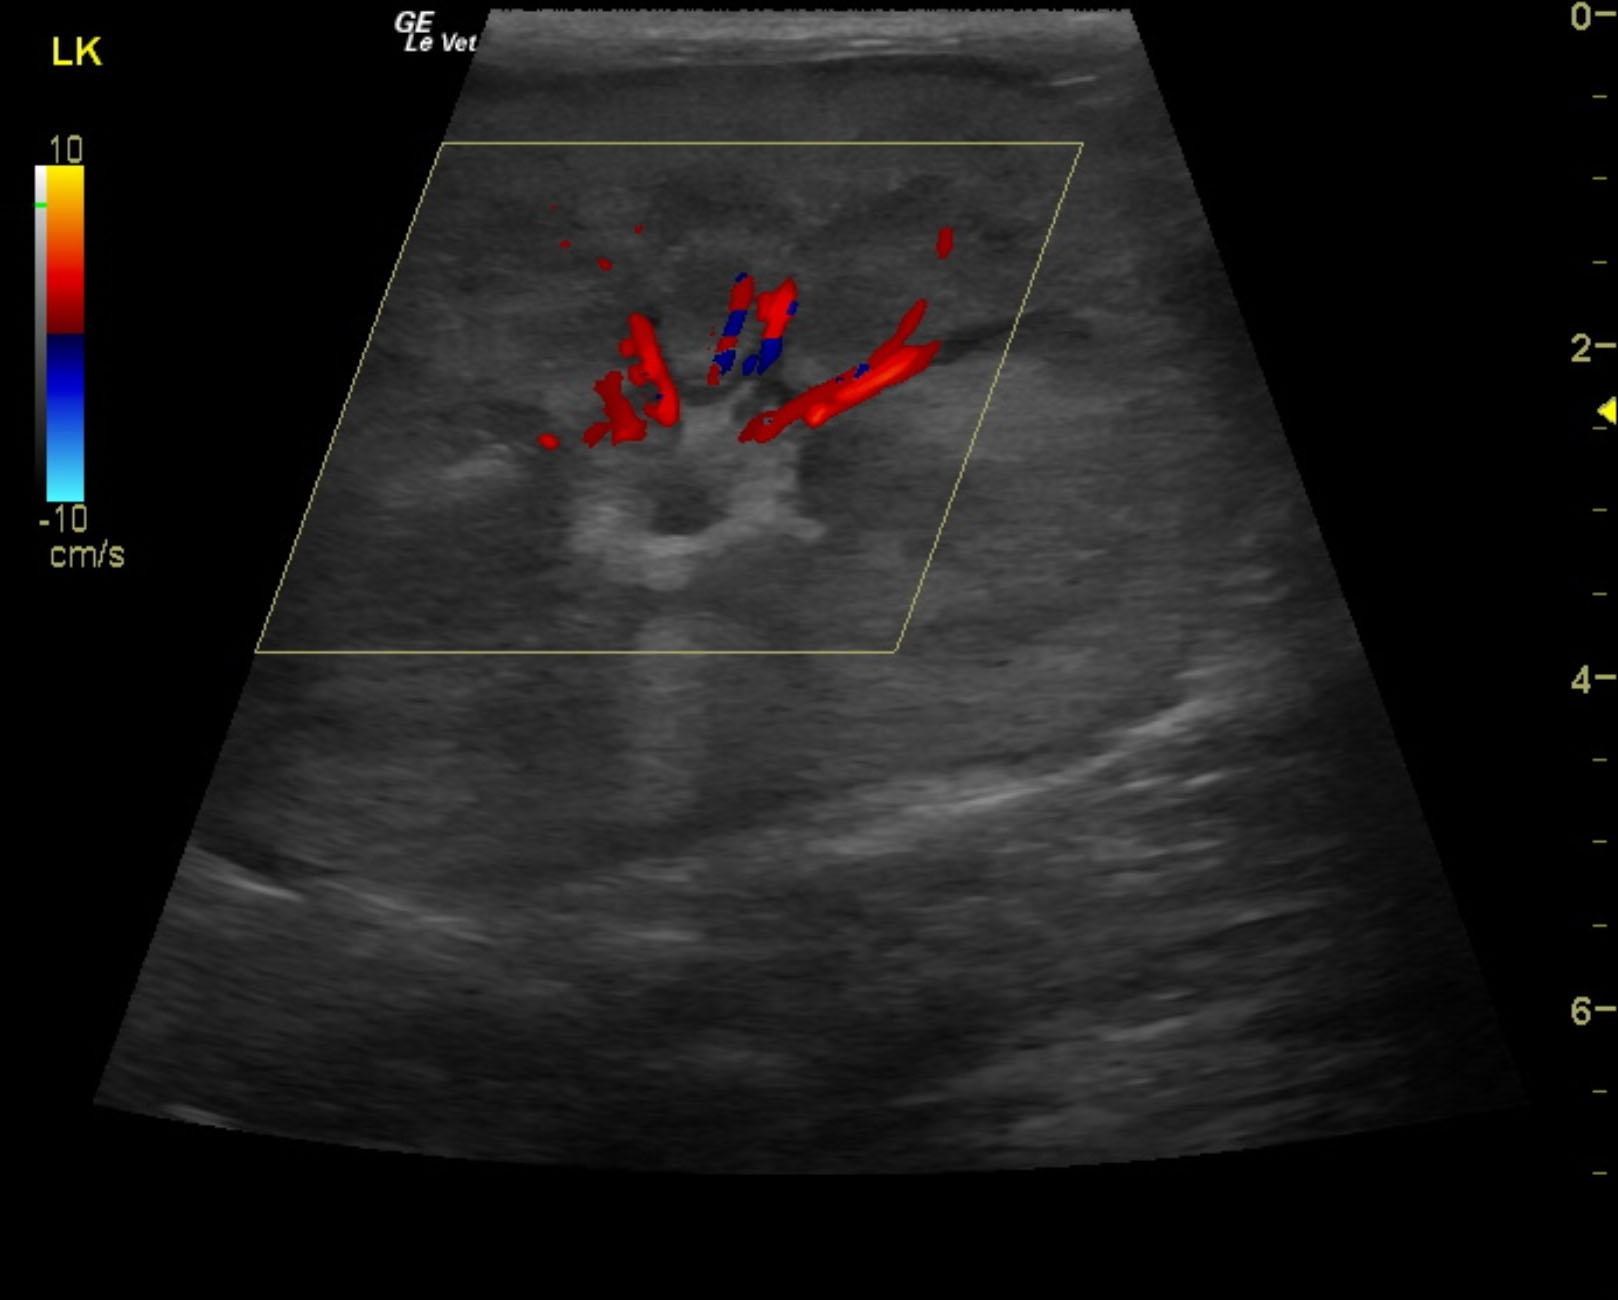

Renal lymphoma in a 10 year old MN DSH cat with renomegaly

A 10-year-old NM DSH was presented for evaluation of renomegaly. Urinalysis showed low SG (1.015) and proteinuria. Azotemia was present in the serum biochemistry.

Ultrasound-guided FNAs were performed of the kidneys. Renal aspirates revealed renal lymphoma.

These images are strongly suggestive for renal lymphoma or similar neoplasia.

Image Interpretation

The kidneys were bilaterally enlarged with cortical striations and loss of corticomedullary definition. Both kidneys presented subcapsular capping (thin hypoechoic line below renal capsule) with fluid accumulation or proliferative neoplastic tissue. The right kidney measured 6.7 cm. The left kidney measured 6.8 cm.